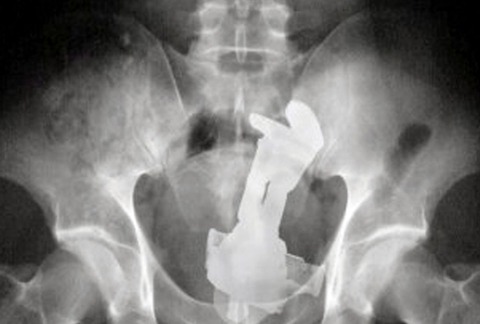

【画像】とんでもないものを挿入れてしまった女の子wwwwwwwwwwwwww Twitter Facebook はてブ LINE コピー 2024.11.25 スポンサーリンク 4:以下、?ちゃんねるからVIPがお送りします:2024/11/24(日) 19:19:21.871 ID:T8oWMks60.net 6:以下、?ちゃんねるからVIPがお送りします:2024/11/24(日) 19:20:29.877 ID:oB+idkf50.net >>4 バズ・ライトイヤーっぽくね 7:以下、?ちゃんねるからVIPがお送りします:2024/11/24(日) 19:21:47.752 ID:k/kIp8pW0.net >>6 マジンガーzかも 続きを読む